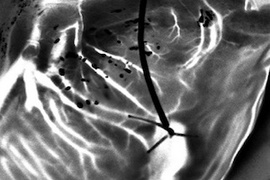

Dynamic speckle reveals details of heart vasculature

Paris-Saclay University technique could help identify organs suitable for transplantation.